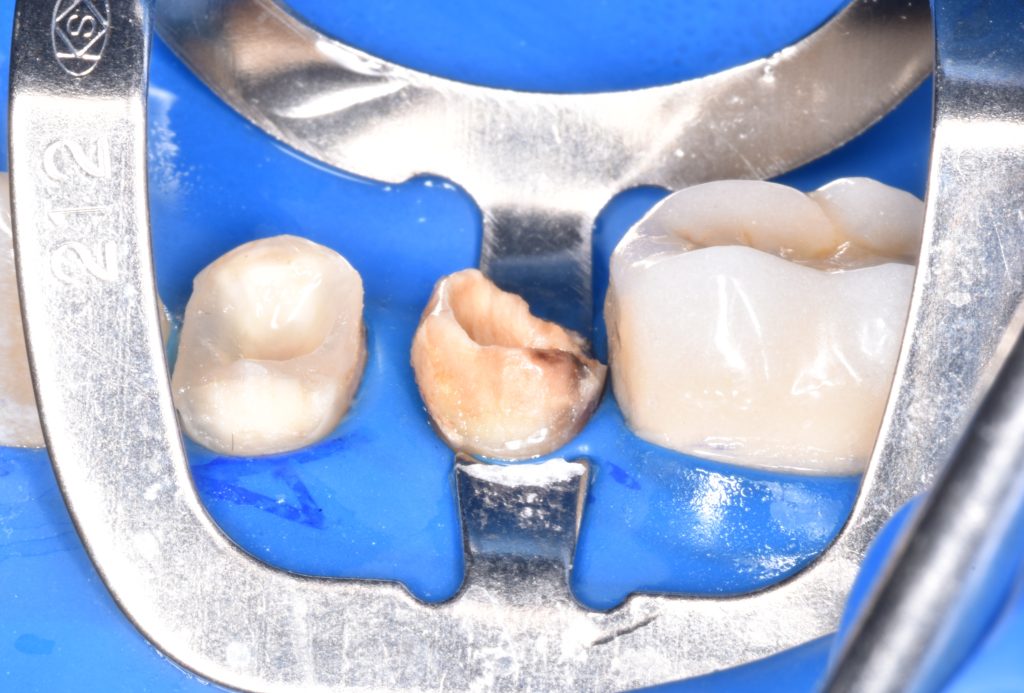

Were badly decayed

Upon examination

Rubber dam isolation is mandatory in such cases

Caries removal with aid of caries detector dye